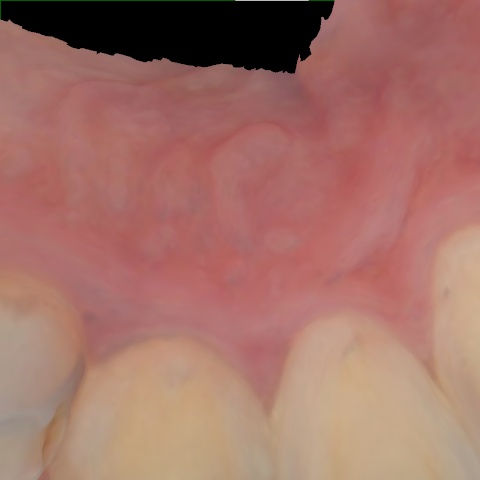

Image 1528 / 1535

NHD39990

Annotated as "Good"

Original Image Rendering Image